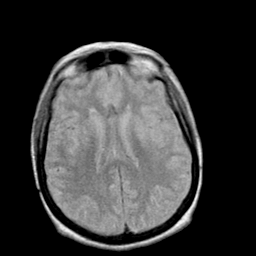

Creutzfeld-Jakob disease: proton density-weighted MR -- Slice #14

[Home][Help][Clinical] Slice 14